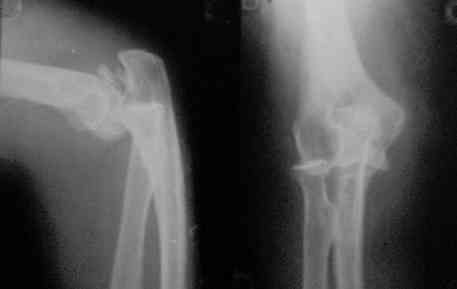

Вывих предплечья

Доброго времени суток, коллеги! Поступила больная2 дня назад (см. снимки).

Вывих вправил, сделал КТ и... появился ряд вопросов: 1.Убирать или оставить отломки? Я думаю убирать2.Каким доступом идти?Что скажете про трасолекрональый?3.Кто какие видел результаты после подобного перелома?4.Что делать с венечным отвостком?5.Нужна ли дополнительная внешняя фиксация?С уважением Д.Б.

А сколько лет больной? Кем работает? Вы уже похоже решили оперировать, тогда, конечно, доступ с пересечением олекранона,Результаты-прогнозировать,тем более заочно,сложно. А что Вы подразумеваете под внешней фиксацией?Гипсовую повязку или аппарат?Лучшая фиксация,если ожидаются проблемы с развитием контрактуры,-аппарат с роликовыми регуляторами и демпфером.